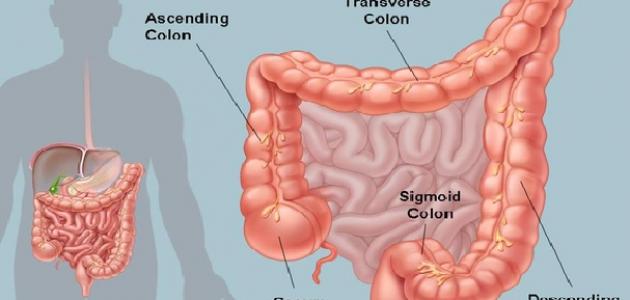

تُعرف الأمعاء الغليظة (بالإنجليزية: Large Intestine) بالقولون (بالإنجليزية: Colon)، ويُعدّ الأعور (بالإنجليزية: Cecum) أول أجزاء القولون، وهو الجزء الذي يرتبط باللفائفيّ (بالإنجليزية: Ileum) الذي يُمثّل آخر أجزاء الأمعاء الدقيقة، ويمكن القول إنّ القولون يُقسم إلى أربعة أجزاء رئيسية، وهي: القولون الصاعد (بالإنجليزية: Ascending Colon) الذي يوجد في الجزء الأيمن من البطن، والقولون المستعرض (بالإنجليزية: Transverse Colon) الذي يقطع البطن، والقولون النازل (بالإنجليزية: Descending Colon) الذي يمثل الجزء الأيسر من البطن، والقولون السينيّ (بالإنجليزية: Sigmoid colon) الذي يقع قبل المستقيم (بالإنجليزية: Rectum) تماماً. وتكمن وظيفة القولون في تصنيع البراز وإنتاجه، وذلك بسحب الماء، والأملاح، وبعض العناصر الغذائية، ومن الجدير بالذكر أنّ هناك مليارات البكتيريا الموجودة في القولون والتي تظلّ في مستوياتٍ تُبقيها متوازنة مع وضع الجسم وحاجته، وتُبطّن القولون مجموعة من العضلات التي تدفع البراز المتكوّن إلى الأجزاء السفلى.[١]